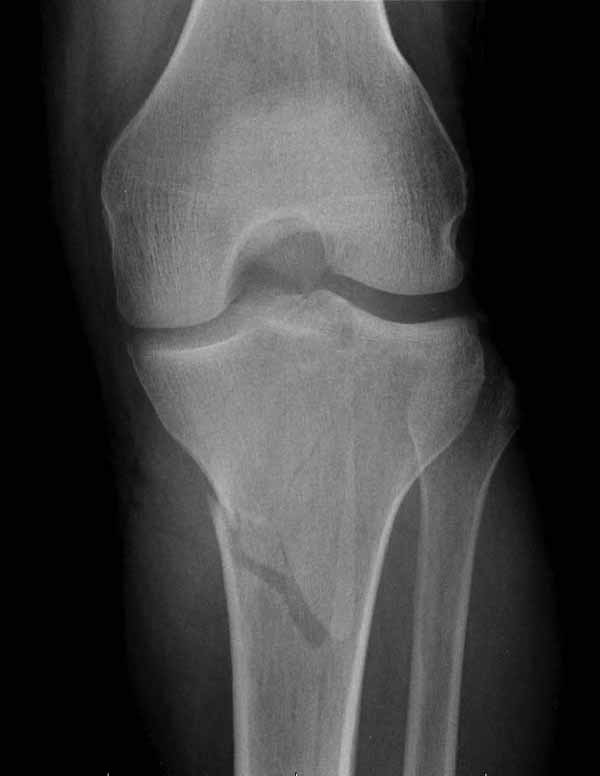

Двухколоннный перелом тибиал плато с вовлечением проксимального диафиза. Внутрисуставной компонент без смещения, и такой перелом можно лечить любым из описанных методов, о которых говорят наши коллеги.

Удобно аппаратом Илизарова или интрамедуллярным гвоздем. Гвозди не так сложно, как пугают, тем более Александр готов помощь с методичкой. Сперва надо установить компрессирующие шурупы на мыщелки. Давно отказались в пользу 3.5-4.0 мм кортикальных вместо толстых спонгиозных, потому что не доказаны преимущества толстых шурупов. Тонкие шурупы в субхондральной зоне смотрятся намного элегантнее, чем толстые 6.5.

Это мероприятие превращает перелом в простой диафизарный, который легко можно фиксировать гвоздем. Шурупы надо установить сзади предполагаемого места введения гвоздя.

Кстати, коллеги правы для уточнения характера перелома надо делать Компьютерную Томографию.